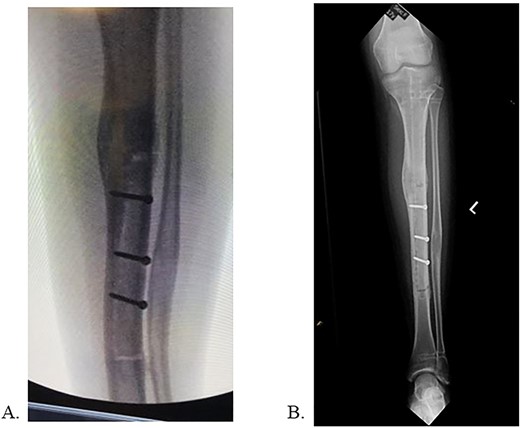

The patient was positioned supine on a radiolucent table with fluoroscopy coming from the contralateral side. The prior infrapatellar scar was incised, revealing bony ingrowth around the proximal end of the implant. A 3.2-mm guide pin was advanced into the center of the implant and a cannulated reamer removed the bony overgrowth. Residual bone surrounding the proximal implant was debrided using a bone curette and then a Nuvasive© conical extractor was attached to the exposed receiving end. The remaining proximal interlocking screw was localized under fluoroscopy and removed. When backslapping the implant, the components disassociated, and the telescopic portion remained lodged in the tibial medullary canal. When consulted intraoperatively, the mother chose to remove all implants by means of tibial osteotomy. An 8 cm long anterior ¼ circumference of the tibia unroofing osteotomy was performed using multiple drill holes and osteotomes (Fig. 2A/B). The remaining portion of the implant was removed with a clamped vice grip and mallet. (Fig. 3A/B). The osteotomy was reduced using a point-to-point reduction clamp and secured with three 2.7-mm lag by technique screws. The wound was irrigated, and 5 cc of demineralized bone matrix was applied to bolster osseous healing.

A: Multi-drill hole technique used to facilitate unroofing osteotomy. B: Completed unroofing osteotomy with visible implant.